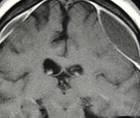

02/12/2024 - Medical NewsBlocking Artery Supplying the Brain Covering After Subdural Hematoma Reduced Repeat Surgery